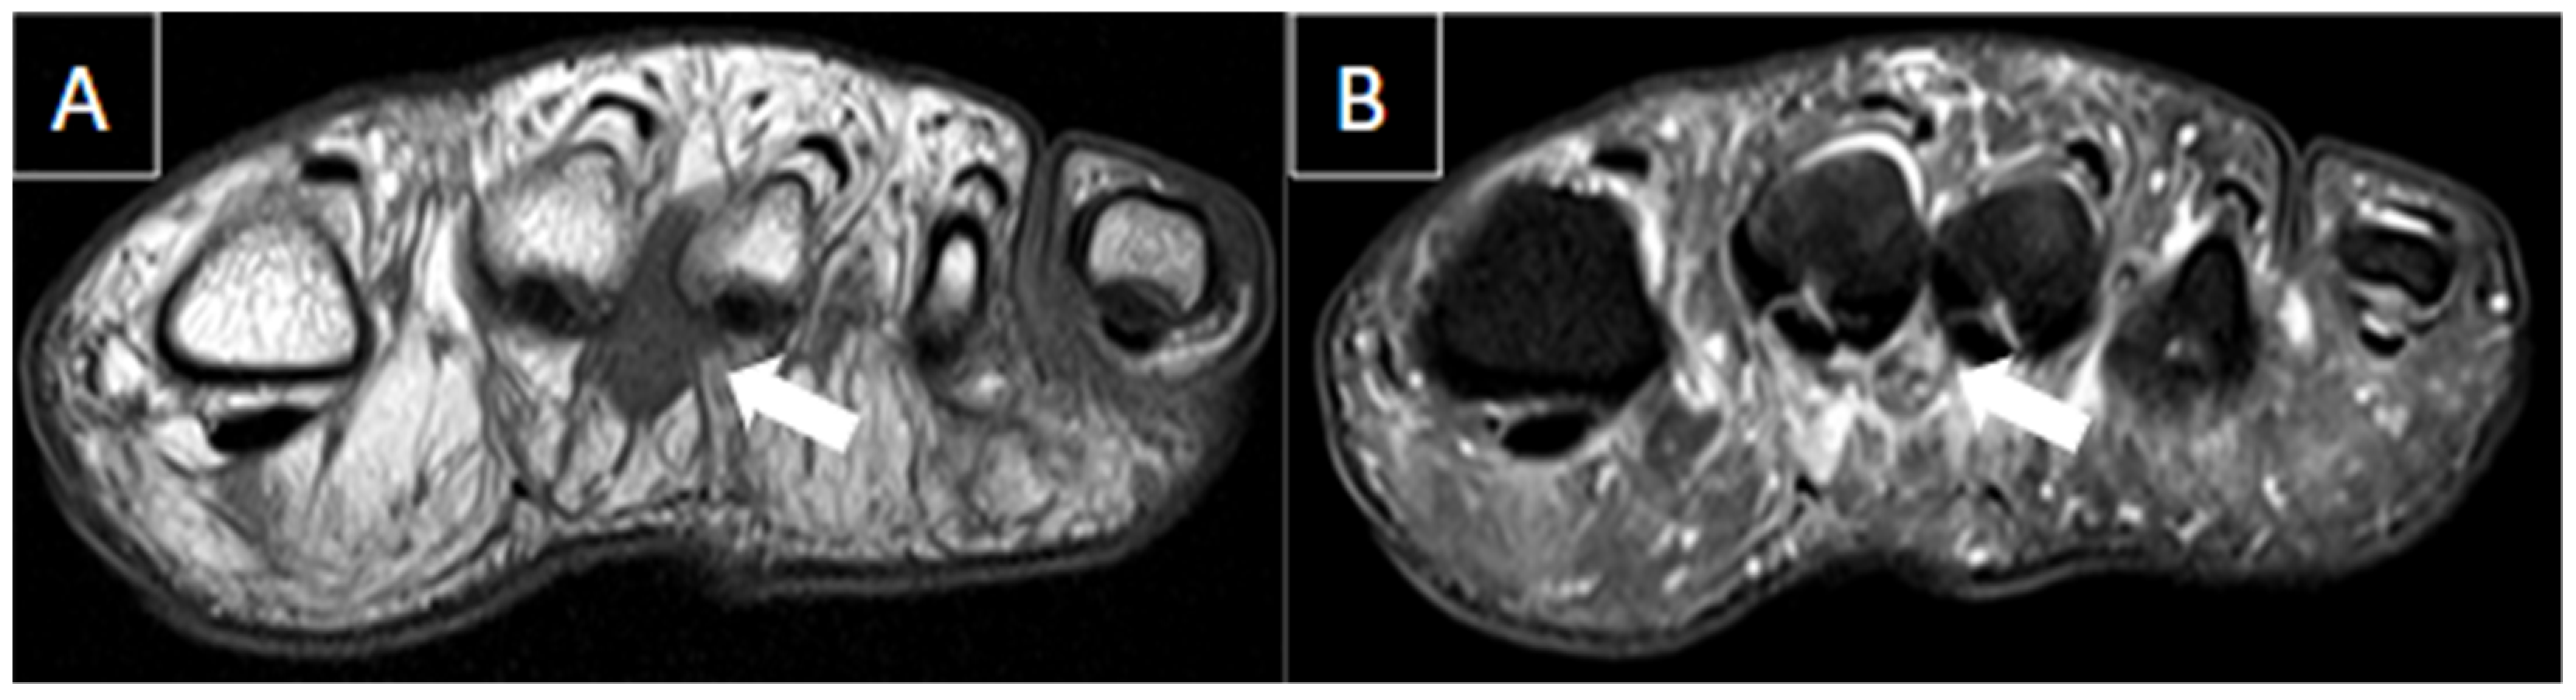

6.1. Intermetatarsal Bursitis

| Morton’s neuroma | Forefoot pain which radiates from the midfoot to toes. Symptoms are often progressive and worsened by activity. | Well-defined ovoid mass with variable echogenicity with continuity with the interdigital nerve in the long axis. The mass can be tender and mobile when compressed, with vascularity on power Doppler. | Hypointense to isointense on T1-weighted images and hypointense to hyperintense on T2-weighted fat-suppressed images. |